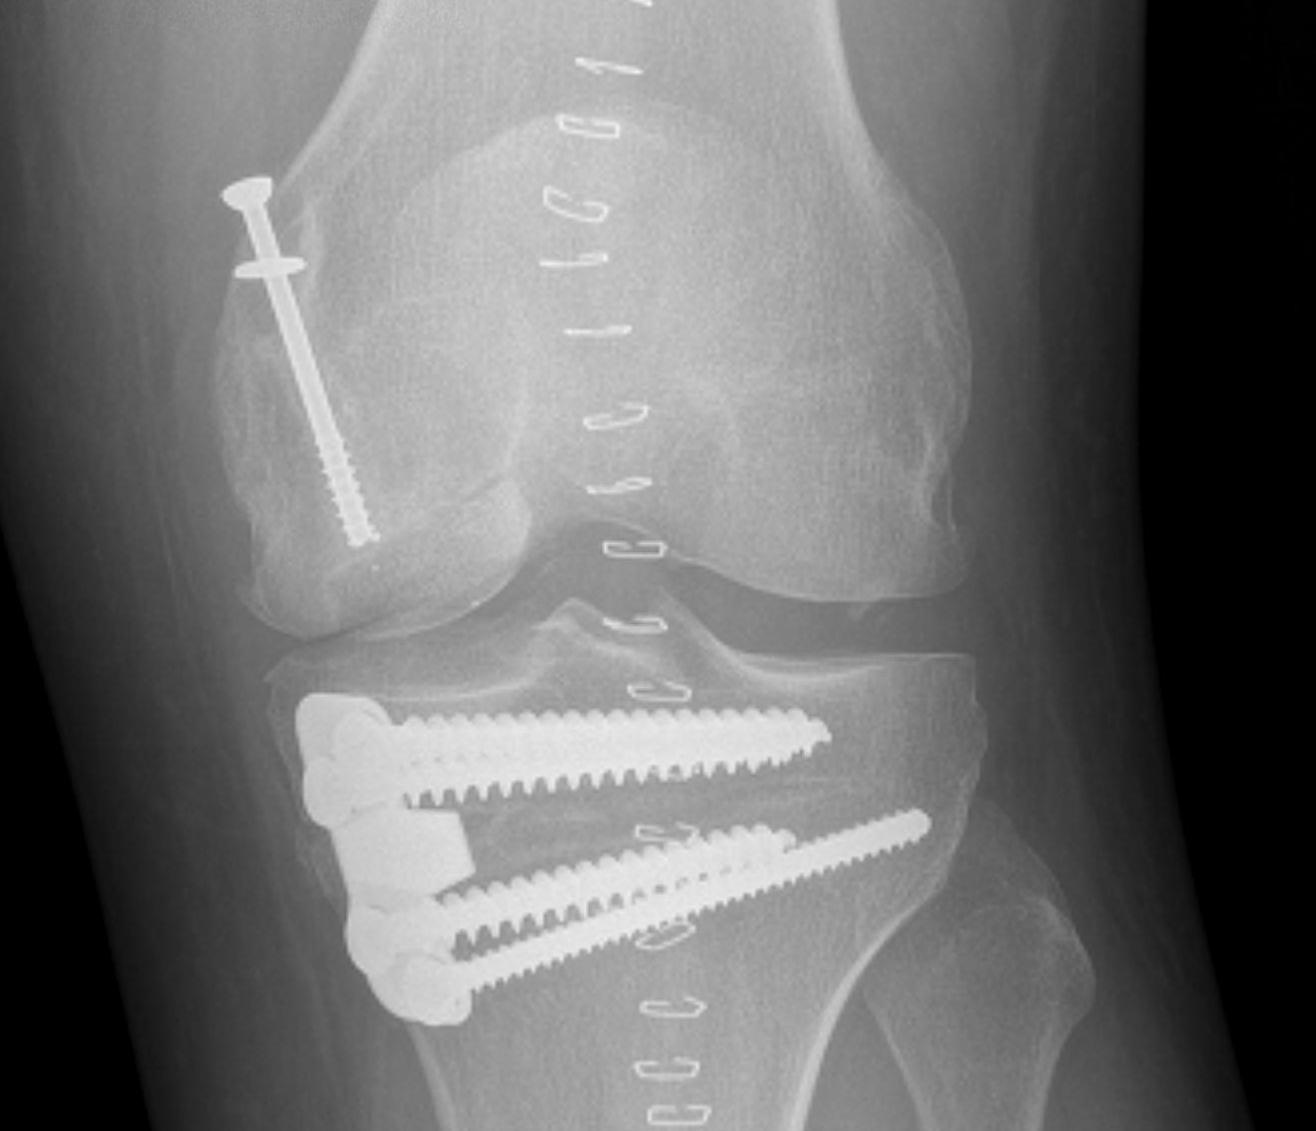

Cartilage defects

• Management